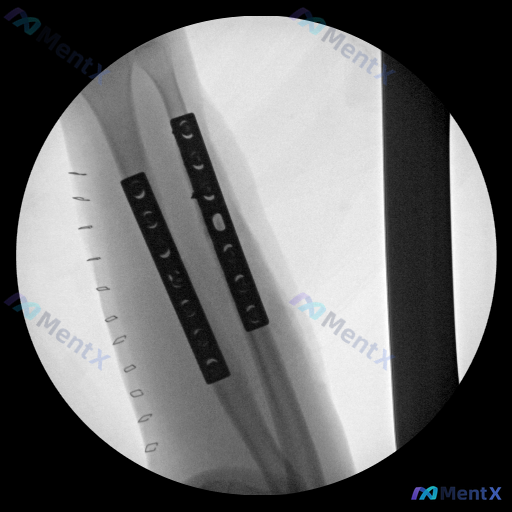

整理到一张小腿部位的影像学资料,是圆形视野,看起来像是术中或术后的透视影像。

- 显示的是胫骨与腓骨的骨干段,都有金属内固定钢板(接骨板)覆盖,能看到螺孔,钢板跨越了可能的骨折或手术区域

- 钢板覆盖区的骨皮质轮廓连续性看起来尚可,没有明显的骨折线延伸到钢板外,但金属伪影干扰比较明显,局部细节(比如骨痂)看不太清楚

- 骨干走行基本符合解剖形态,没有明显的成角畸形或侧方明显移位

- 右侧能看到一排细条状的高密度影,像是手术切口的缝合钉

- 除了钢板、螺钉(部分细节和钢板重叠)和缝合钉之外,没看到其他异常的高密度异物